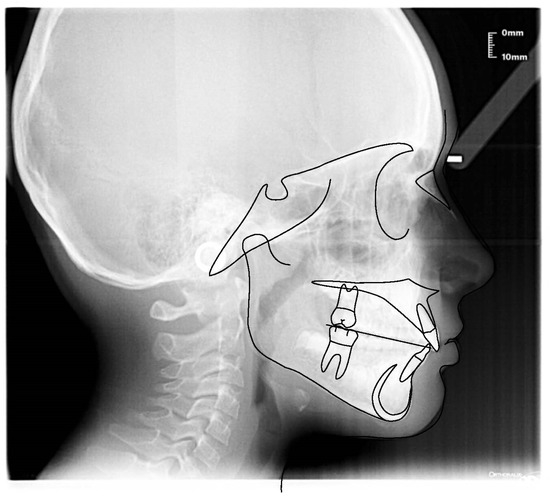

3.3. Clinical Case #3

| Cephalometric Analysis before Treatment | Val | Dev | Min | Med | Max | Diff |

|---|---|---|---|---|---|---|

| SNA | 82.4° | N | 80° | 82° | 84° | 0° |

| SNB | 74.7° | −xx | 78° | 80° | 82° | 3.3° |

| ANB | 7.7° | xx | 0° | 2° | 4° | 3.7° |

| sna-snp^Go-Gn | 23.2° | N | 15° | 20° | 25° | 0° |

| S-N^sna-snp | 10.6° | N | 7° | 10° | 13° | 0° |

| S-N^PO | 20.6° | xx | 11° | 14° | 17° | 3.6° |

| S-N^Go-Gn | 33.7° | N | 27° | 32° | 37° | 0° |

| SNBa | 127.1° | N | 124° | 129° | 134° | 0° |

| SND | 71.1° | −xx | 74° | 76° | 78° | 2.9° |

| IS^II | 103° | −xxxxx | 125° | 130° | 135° | 22° |

| IS:N-A | 2.9 | −x | 3 | 4 | 5 | 0.1 |

| II:N-B | 4.8 | N | 3 | 4 | 5 | 0 |

| II:A-Pog | 0.8 | N | −1 | 1 | 3 | 0 |

| Ls:Line S | 2.6 | xx | −1 | 0 | 1 | 1.6 |

| Li:Line S | 0.6 | N | −1 | 0 | 1 | 0 |

| Cvm:S-Gn | −3.3 | −xxx | −1 | 0 | 1 | 2.3 |

| Mol Sup^P. Occl | 109° | xxx | 88° | 90° | 92° | 17° |

| N-S-Cop | 118.3° | N | 117° | 122° | 127° | 0° |

| S-Cop-Go | 156.4° | xx | 137° | 143° | 149° | 7.4° |

| Cop-Go-Gn | 119° | N | 115° | 120° | 125° | 0° |

| Cop-Go-N | 48.5° | N | 48° | 50° | 52° | 0° |

| N-Go-Gn | 70.5° | N | 68° | 70° | 72° | 0° |

| II^Go-Gn | 104.1° | xxx | 92° | 93° | 94° | 10.1° |

| SOr:sna | 57.5 | 0 | 0 | 0 | 57.5 | |

| sna:Me | 54.1 | 0 | 0 | 0 | 54.1 | |

| S:N | 63.2 | −xxx | 71 | 74 | 77 | 7.8 |

| snp:A | 44.4 | 0 | 0 | 0 | 44.4 | |

| Go:Me | 59 | −xxx | 69.3 | 74.3 | 79.3 | 10.3 |

| Wits | 4.2 | xx | −2 | 0 | 2 | 2.2 |

| IS^N-S | 119.1° | xxx | 101° | 103° | 105° | 14.1° |

| Pog:N-B | 1.6 | 0 | 0 | 0 | 1.6 | |

| Pog:N-B—II:N-B | −3.2 | - | 0 | 0 | 0 | 3.2 |

| Cephalometric Analysis after Treatment | Val | Dev | Min | Med | Max | Diff |

| SNA | 79.5° | −x | 80° | 82° | 84° | 0.5° |

| SNB | 76.4° | −x | 78° | 80° | 82° | 1.6° |

| ANB | 3.2° | N | 0° | 2° | 4° | 0° |

| sna-snp^Go-Gn | 23.3° | N | 15° | 20° | 25° | 0° |

| S-N^sna-snp | 11.4° | N | 7° | 10° | 13° | 0° |

| S-N^PO | 20.1° | xx | 11° | 14° | 17° | 3.1° |

| S-N^Go-Gn | 34.7° | N | 27° | 32° | 37° | 0° |

| SNBa | 136.4° | x | 124° | 129° | 134° | 2.4° |

| SND | 72.1° | −x | 74° | 76° | 78° | 1.9° |

| IS^II | 122° | −x | 125° | 130° | 135° | 3° |

| IS:N-A | 4 | N | 3 | 4 | 5 | 0 |

| II:N-B | 3.5 | N | 3 | 4 | 5 | 0 |

| II:A-Pog | 2.1 | N | −1 | 1 | 3 | 0 |

| Ls:Line S | −2 | −xx | −1 | 0 | 1 | 1 |

| Li:Line S | 0 | N | −1 | 0 | 1 | 0 |

| Cvm:S-Gn | −0.1 | N | −1 | 0 | 1 | 0 |

| Mol Sup^P. Occl | 95.8° | xx | 88° | 90° | 92° | 3.8° |

| N-S-Cop | 129.4° | x | 117° | 122° | 127° | 2.4° |

| S-Cop-Go | 141.5° | N | 137° | 143° | 149° | 0° |

| Cop-Go-Gn | 123.8° | N | 115° | 120° | 125° | 0° |

| Cop-Go-N | 52.5° | x | 48° | 50° | 52° | 0.5° |

| N-Go-Gn | 71.3° | N | 68° | 70° | 72° | 0° |

| II^Go-Gn | 99.9° | xxxxxx | 92° | 93° | 94° | 5.9° |

| SOr:sna | 57.1 | 0 | 0 | 0 | 57.1 | |

| sna:Me | 56.3 | 0 | 0 | 0 | 56.3 | |

| S:N | 62.9 | −xxx | 71 | 74 | 77 | 8.1 |

| snp:A | 46.7 | 0 | 0 | 0 | 46.7 | |

| Go:Me | 61 | −xx | 69.3 | 74.3 | 79.3 | 8.3 |

| Wits | −0.8 | N | −2 | 0 | 2 | 0 |

| IS^N-S | 103.4° | N | 101° | 103° | 105° | 0° |

| Pog:N-B | 0.4 | 0 | 0 | 0 | 0.4 | |

| Pog:N-B—II:N-B | −3.1 | - | 0 | 0 | 0 | 3.1 |